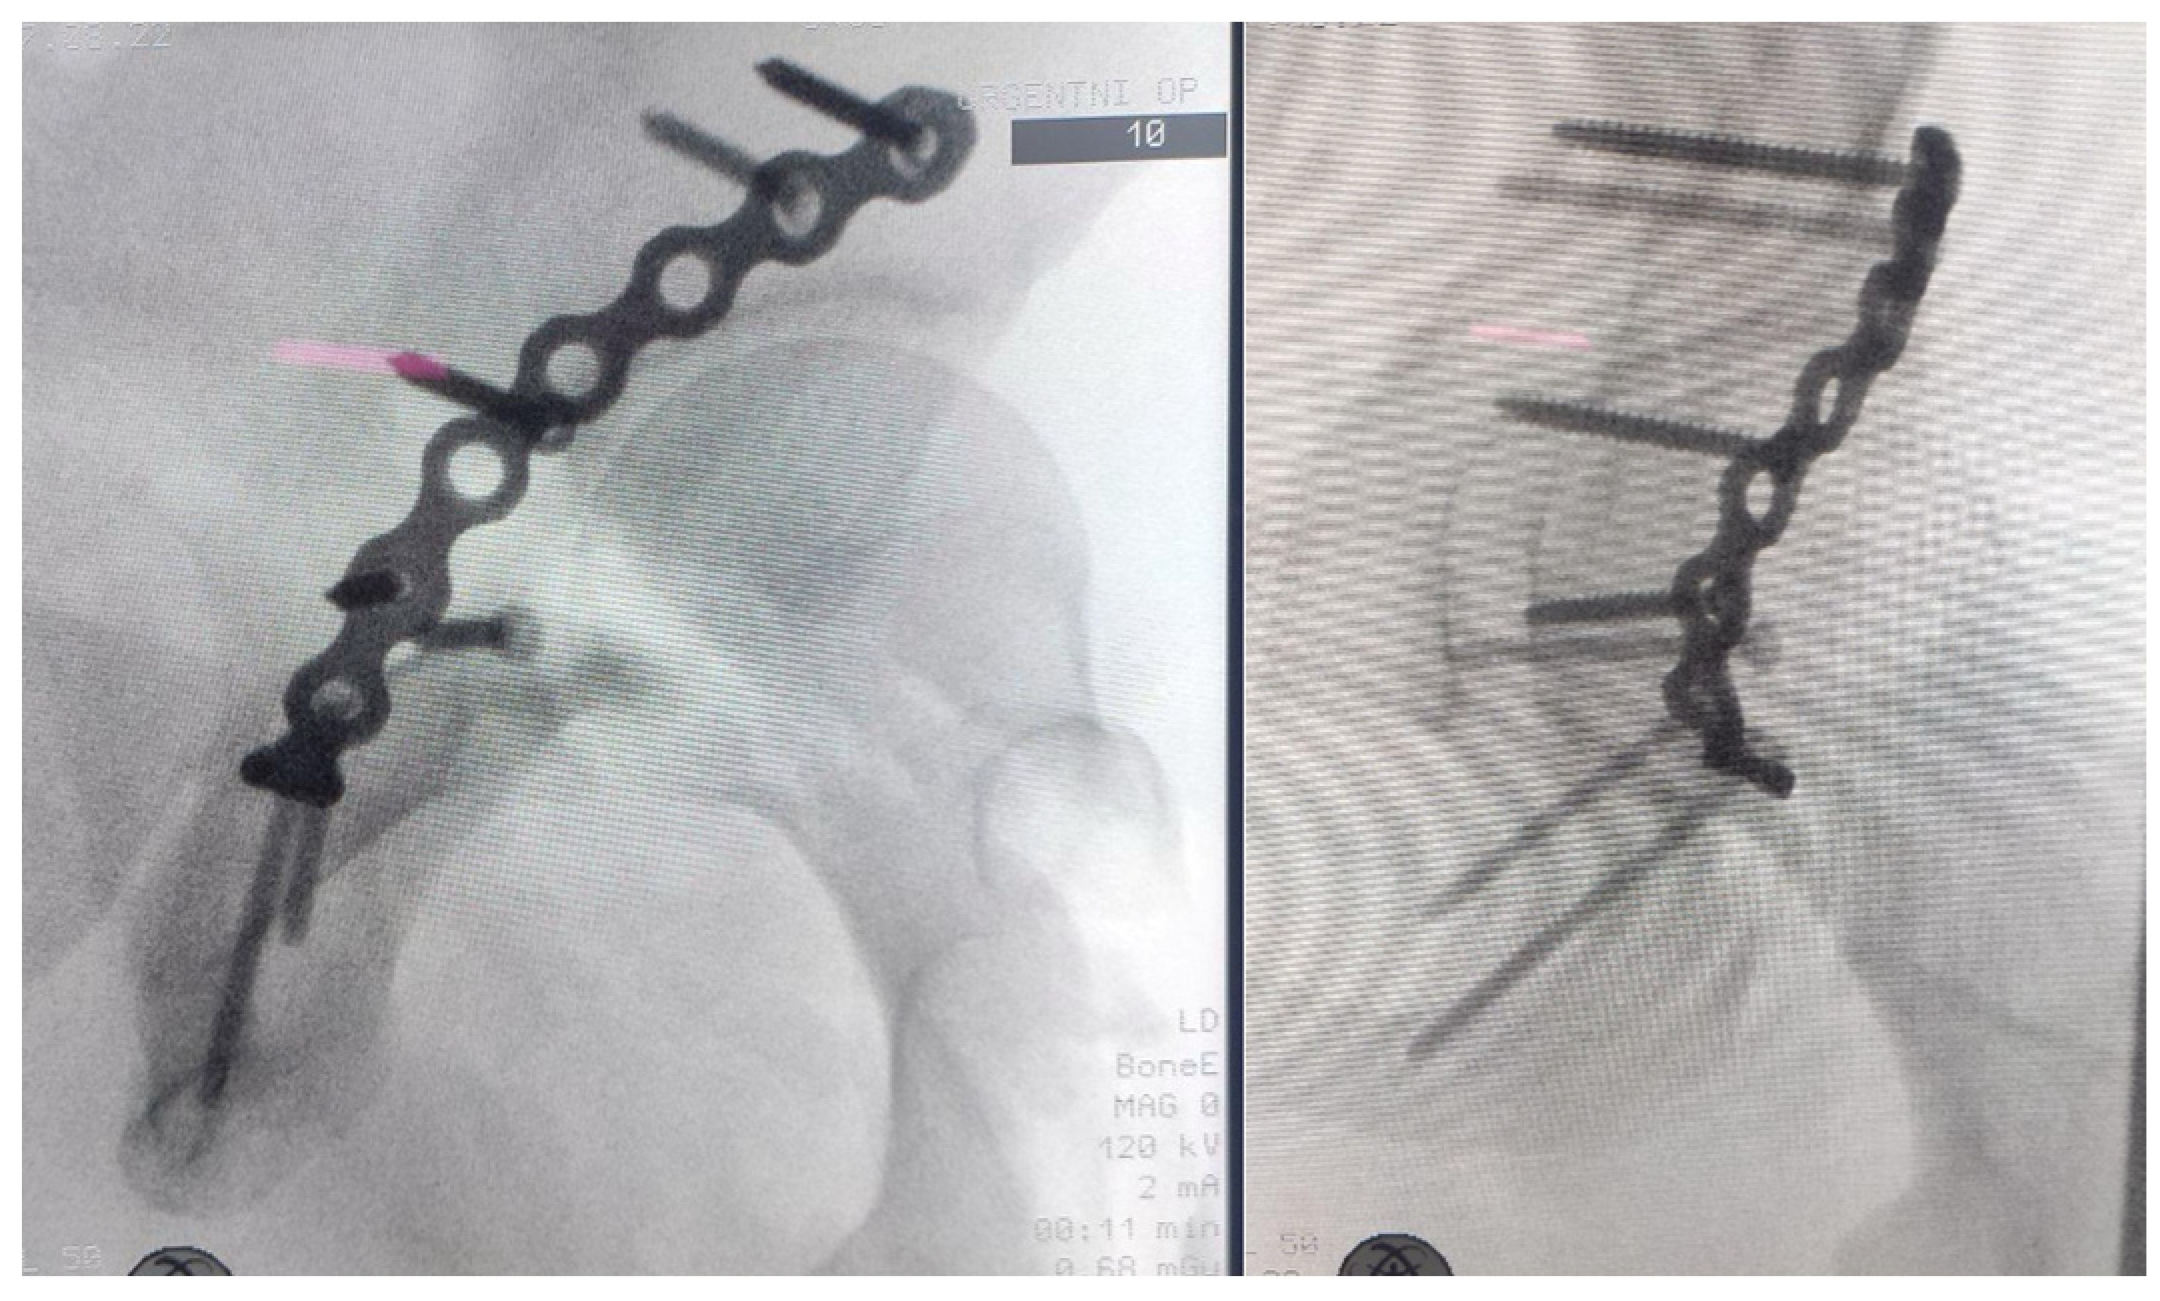

Subsequent multislice computed tomography (MSCT) of the pelvis with 3D reconstruction provided enhanced visualization of the osseous and articular morphology (Figure 2), confirming the following:

• Right posterior wall acetabular fracture, with an estimated >25% involvement of the weight-bearing dome, necessitating surgical intervention.

• No femoral head fractures, intra-articular fragments, or marginal impaction.

• No sacroiliac joint disruption or pelvic ring instability.

Figure 2. MSCT of the pelvis with 3D reconstruction showing right posterior wall acetabular fracture and confirming there are no femoral head fractures, intra-articular fragments, marginal impaction, nor pelvic ring disruptions.